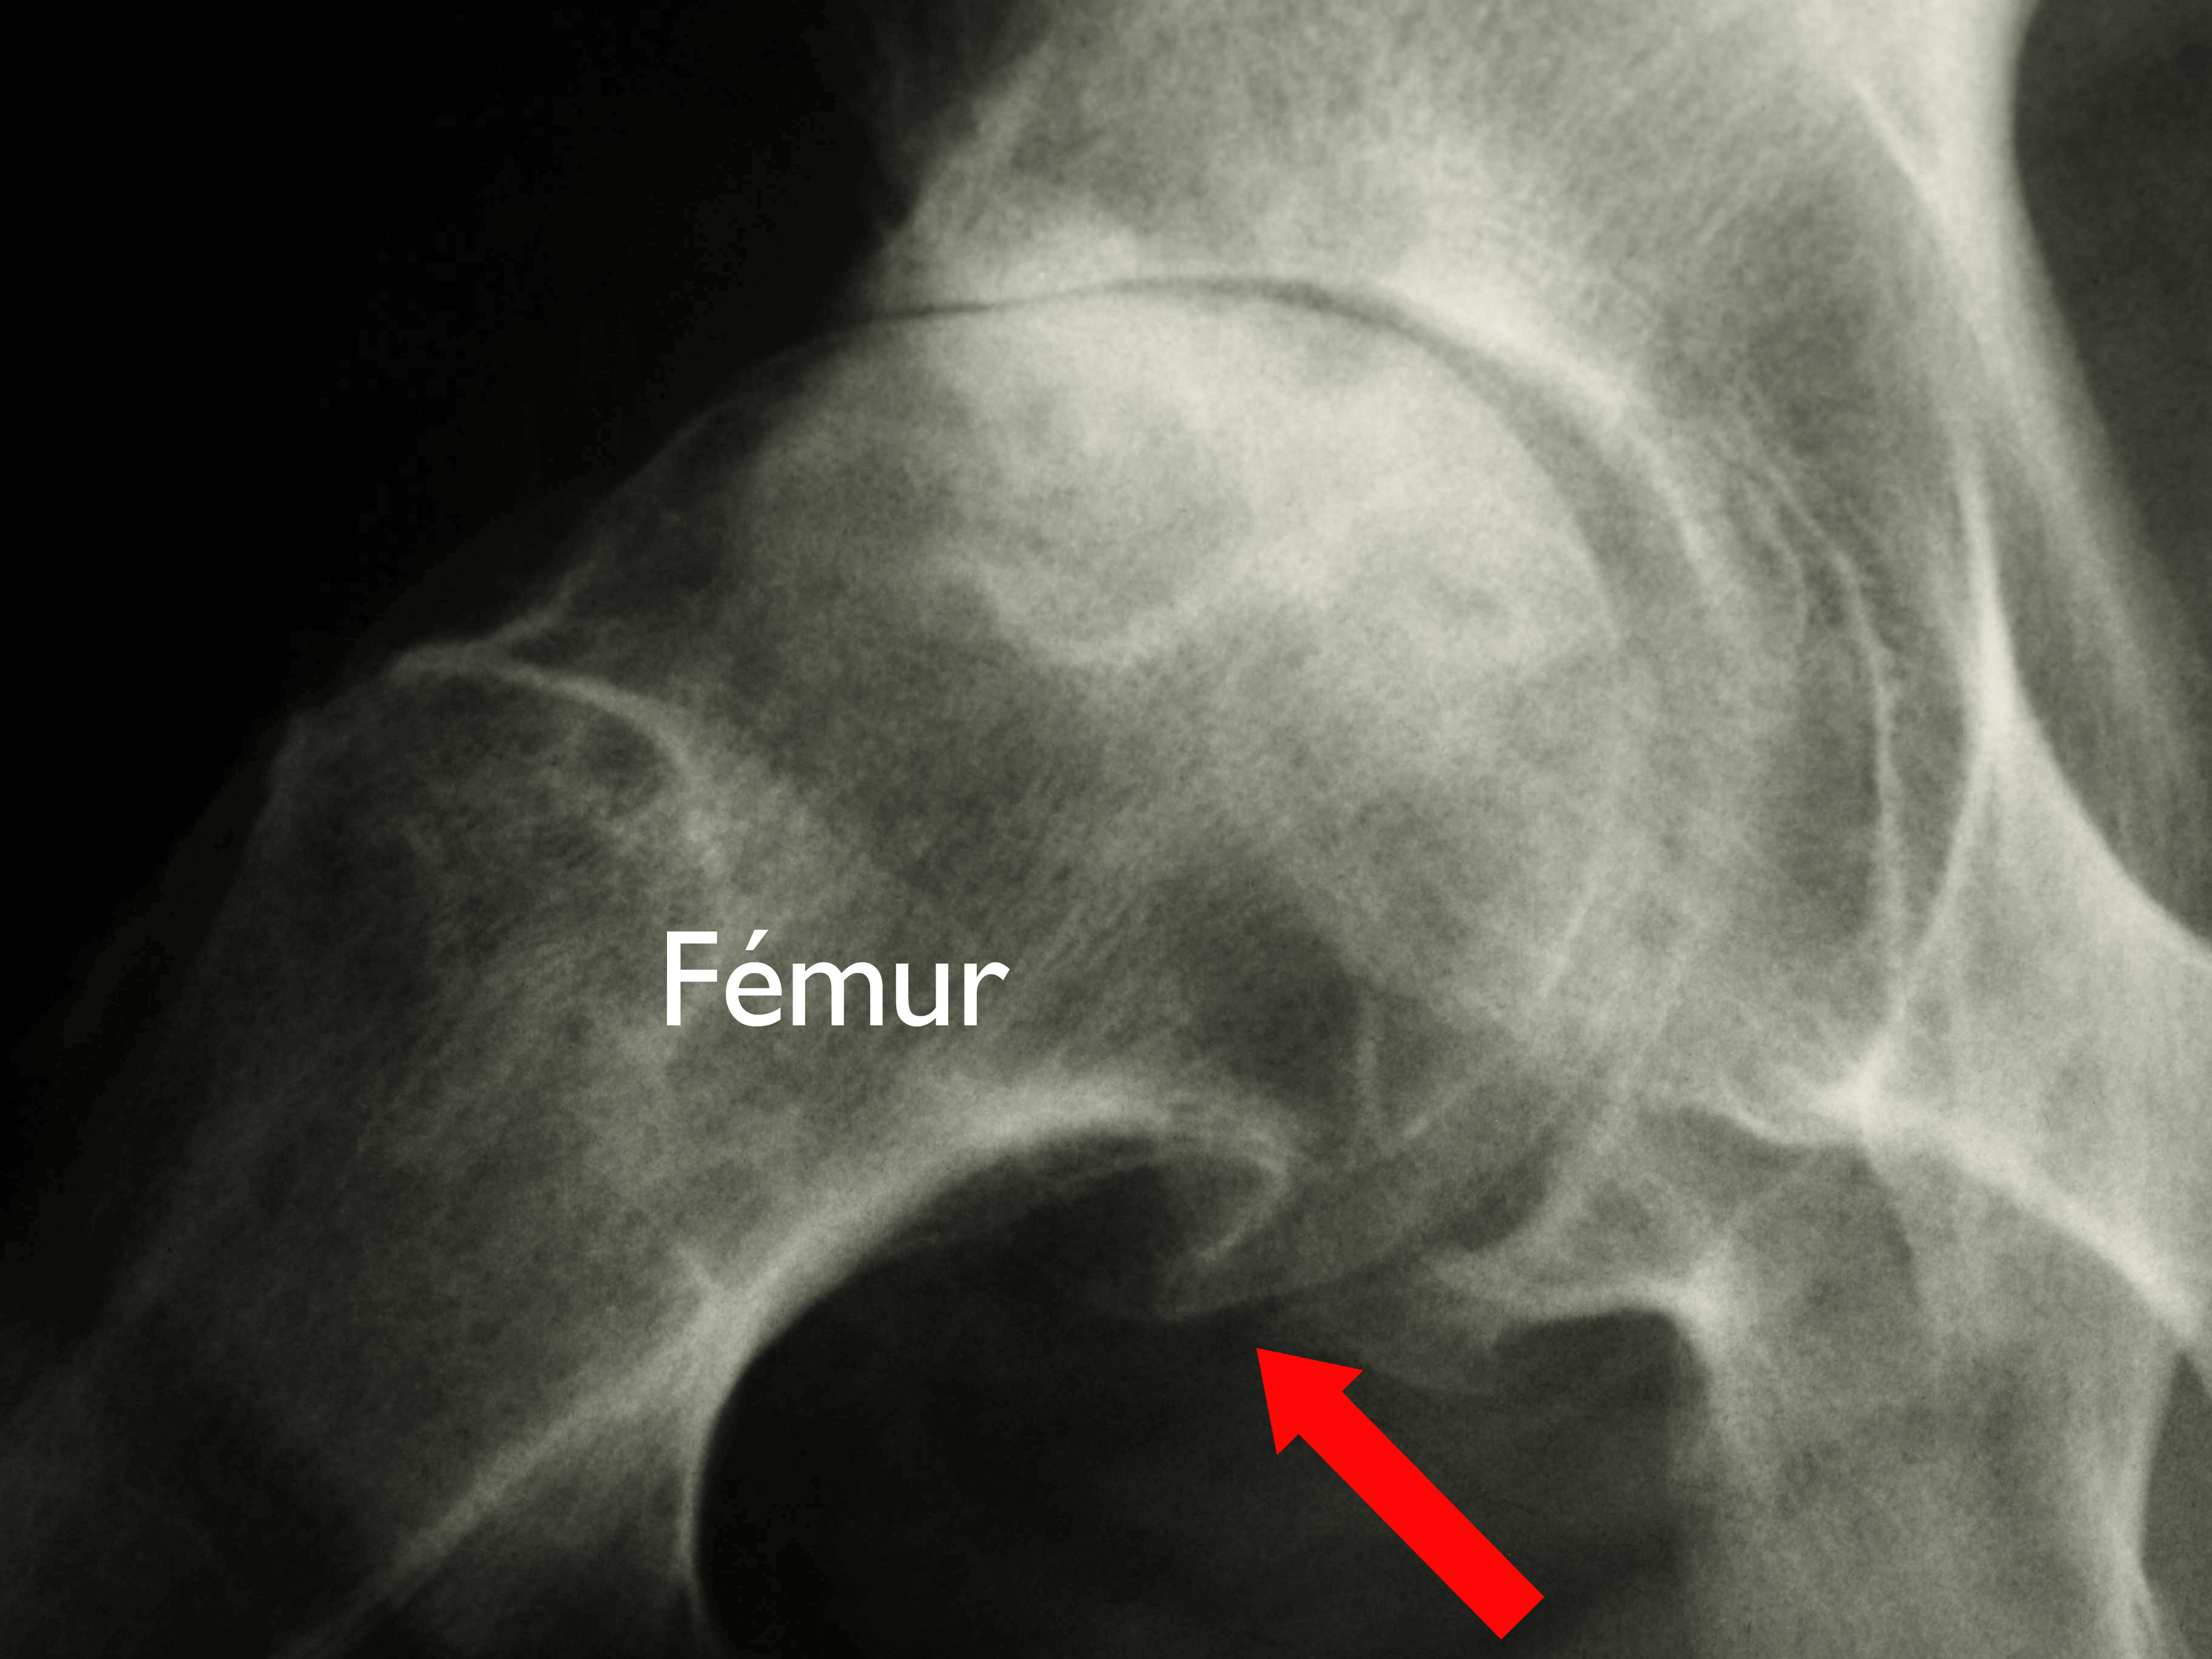

Radiografías. Con las radiografías se pueden obtener imágenes detalladas de las estructuras densas, como los huesos. Las radiografías de la cadera con artrosis pueden mostrar el estrechamiento del espacio articular y la formación de protuberancias óseas (osteofitos).

En esta radiografía de una cadera con artrosis, la flecha indica una protuberancia ósea (osteofito) grande en la parte inferior de la cabeza femoral.